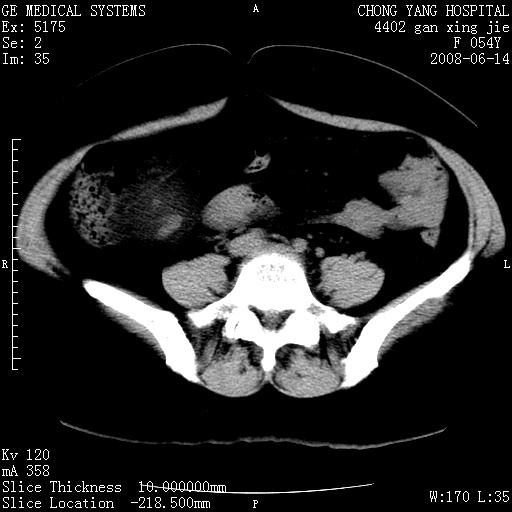

标题: CT14033:F54Y,来源哪? 外伤发现,自述既往无不适。 [打印本页]

标题: CT14033:F54Y,来源哪? 外伤发现,自述既往无不适。

1、脂肪肝。2、腹腔囊性占位,首考虑来源于右肾下极,其次考虑来源于肠系膜。

考虑肠系膜囊肿,脂肪肝

肠囊肿可能性大,与十二直肠水平部呈喇叭口,来源于十二直肠,不排除胰头假囊肿.

1、脂肪肝。2、腹腔囊性占位,首考虑肠源性囊肿或中肾管囊肿。

脂肪肝,来源于腹膜后囊肿可能性大。

脂肪肝,巨大肾囊肿

支持考虑肠系膜囊肿,脂肪肝.

考虑肠系膜囊肿

1)脂肪肝。2)右肾下极巨大囊肿。

右肾下极巨大囊肿可能性大。

右中下腹部囊性肿块,与右肾下极关系密切,考虑右肾下极巨大外生性囊肿;脂肪肝。